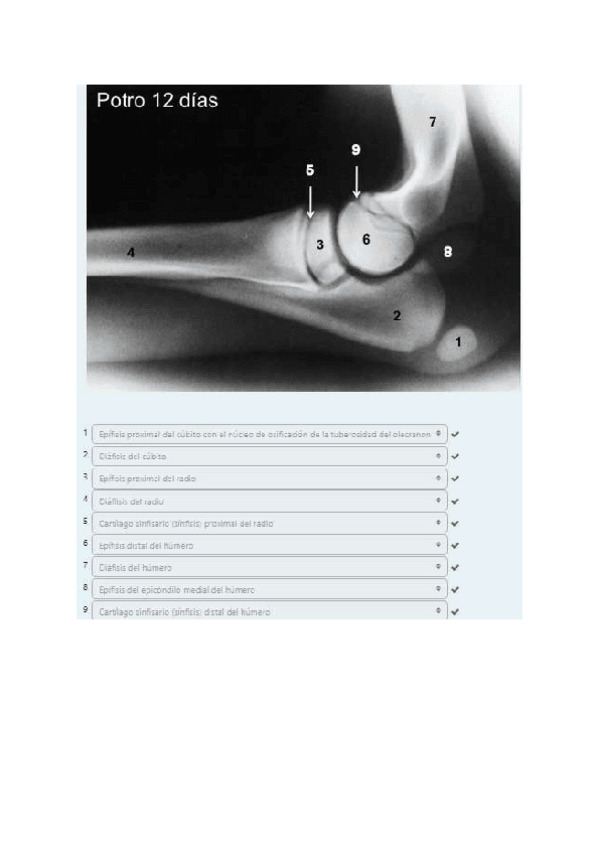

He publicado nuevos apuntes de 1º EMBRIOLOGÍA Y ANATOMÍA I: Radiografías práctica 6.pdf

8 páginas

He publicado nuevos apuntes de 1º EMBRIOLOGÍA Y ANATOMÍA I: SOLUCION-RADIOGRAFIAS-COMPLETAS.pdf

61 páginas

He publicado nuevos apuntes de 1º EMBRIOLOGÍA Y ANATOMÍA I: Todas-las-radiografias-de-anatomia-para-estudiar.pdf

129 páginas